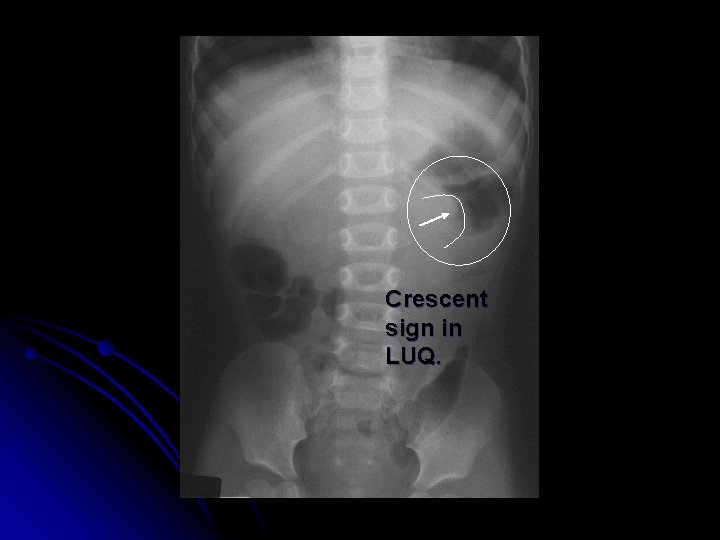

Diagnosis & Treatment l Abdominal plain films: l Crescent sign l Target sign l Ultrasonography: l Bull’s eye sign l Coiled spring sing l Target sign l CT scan (3 -1)

Crescent sign in LUQ.